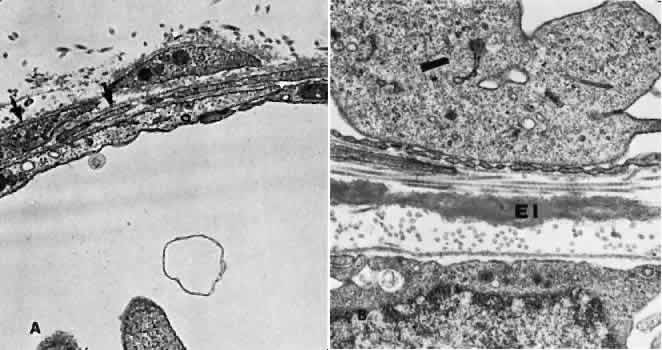

Retinal Veins and Venules Retinal veins are present in the inner retina, where they occasionally interdigitate with their associated arteries. When the two vessels cross, the artery usually lies anterior (toward the vitreous) to the vein.16 About one third of the time, however, the vein is anterior. At such crossing sites, the two vessels share a common adventitial coat.17 Under normal circumstances, the crossing vein's lumen may be decreased by as much as one third as a result of compression from the accompanying artery.17 There are many more arteriovenous crossings temporally than nasally, because the nasal vessels assume a much straighter course. Arteriovenous crossings are important because they represent the most common site of branch retinal vein obstructions. The separation of the superior and inferior halves of the perfusion of the retina is mirrored in the venous drainage pattern as well. Rarely does a retinal vein cross the horizontal raphe under normal circumstances. The retinal veins drain into the CRV, which also acts as the major efferent channel for the vessels of the optic nerve. Near the disc, the retinal veins are approximately 150 μm in diameter. Throughout the retina, the veins and venules generally follow the course of the arteries and arterioles. The intima of the veins consists of a layer of endothelial cells surrounded by a basement membrane continuous with that of the innermost layer of smooth muscle cells of the media. The media of the largest veins in the posterior retina consists of several layers of longitudinally oriented smooth muscle cells. The adventitia makes up the greatest part of the vessel wall and consists of loosely arranged collagen fibers and adventitial cells and is in direct contact with the glial cells of the retina. Venules are usually less than 20 μm in diameter.15 The media is composed of a single layer of cells resembling pericytes, containing poorly developed myofilaments and dense bodies. Elastin is not present. The adventitia contains little other than the basement membrane surrounding the pericyte (Fig. 5). Retinal Capillaries Throughout most of the posterior retina, the retinal capillaries are arranged anatomically in a dual layer. The superficial capillary layer is associated with the ganglion cell layer, whereas the deep capillary layer resides within the inner nuclear layer. Like capillary networks elsewhere in the body, the retinal capillaries assume a meshwork configuration to ensure adequate perfusion to all retinal cells. The deeper layer has a mesh diameter (i.e., the distance betweencapillaries) that characteristically averages 50 μm in diameter but varies between 15 and 130 μm. The more superficial layer has a slightly larger meshwork, on average 65 μm in diameter (16 to 150 μm). In the midequatorial and anterior zones, where the retina is thinner, only one capillary layer is present. In the fovea and the far retinal periphery, retinal capillaries are absent. The precise anatomical localization of the superficial layer of retinal capillaries appears to depend on the thickness of the accompanying ganglion cell layer.18 In the foveola itself and in the immediate parafoveal retina that contains a ganglion cell layer less than 15 μm thick, there are no superficial capillaries. This area represents the foveal avascular zone. Pathologic conditions that feature retinal capillary dropout, such as diabetes mellitus and sickle cell disease, may show an enlargement of this foveal avascular zone. Near the foveal margin, where the ganglion cell layer is of moderate thickness, the superficial retinal capillaries can be found in the outer aspect of the ganglion cell layer. In the intermediate parafoveal area, which has a ganglion cell region thicker than 45 μm, the superficial retinal capillaries are present within the ganglion cell layer itself. In the perifoveal region, where the ganglion cell layer is two to four cells thick, the superficial capillaries are found along the inner boundary of the ganglion cell layer, in contact with the nerve fiber layer. The major retinal vessels, especially the larger ones, usually are in contact with both the inner and outer boundaries of the ganglion cell layer. A capillary-free zone is present around each of the larger retinal arteries and veins (Fig. 6). It is more prominent around the arteries, measuring up to 100 μm. The capillary-free zone is a product of the embryologic vascular remodeling process. Direct diffusion of oxygen through the walls of the large retinal vessels probably initiates this process of vascular remodeling. Embryologically, numerous capillary-sized channels retract from the developing artery, leaving only a relatively few right-angled side-arm channels to serve as precapillary arterioles. In keeping these side channels to a minimum, the maintenance of an adequate pressure head for the remainder of the retina is ensured. In contrast, the radial peripapillary capillaries (RPCs) may develop in a different fashion, later than the other capillary beds, after vascular remodeling has already occurred.19 A distinct layer of capillaries, the RPC, is found adjacent to the optic disc, most prominently in the superior and inferior temporal aspects of the posterior pole (Fig. 7).20 These capillaries originate only from intraretinal arterioles and not from the optic disc vasculature. They are found within the inner aspect of the nerve fiber layer, making them the most superficial of all retinal capillaries. The RPCs tend to follow relatively long, straight paths, having few anastomoses with adjacent or underlying capillary beds. The RPCs do not traverse the central macular area. Their distribution suggests some anatomical correlation with various diseases. Cotton-wool spots are found in a distribution similar to the RPCs, and the arcuate scotoma seen in glaucoma appears to correspond to their pattern as well.21 The superficial peripapillary hemorrhages seen in glaucoma (Drance hemorrhages) may originate with the RPCs as well.22 Retinal capillaries range in diameter from 4 to6 μm. The capillaries throughout the retina, including those of the radial peripapillary network, have the same fine structure.23 The capillary wall consists of a continuous layer of flattened and longitudinally oriented endothelial cells and an incomplete layer of longitudinally oriented pericytes (Fig. 8). The pericytes (formerly referred to as mural cells) are closely spaced, resulting in an approximate ratio of pericytes to endothelial cells of 1:1, a relatively high ratio compared with elsewhere in the central nervous system. Ultrastructural examination of the endothelial cells of retinal capillaries shows that the cytoplasm of the cell bulges in the region of the nucleus. This area contains the Golgi apparatus, centrioles, and rough-surfaced endoplasmic reticulum. The remainder of the cytoplasm contains moderate amounts of smooth endoplasmic reticulum and mitochondria. The average endothelial cell thickness is 236 nm. Pinocytotic vesicles occur in the cells of the retinal capillaries. The vesicles are of uniform size, with an average diameter of 70 nm. Pinocytotic vesicles are found on the lumen (10% of total) and basement membrane (28%) side of the endothelial cells and free in the cytoplasm (62%). Approximately 2% of the volume of the endothelial cell is occupied by pinocytotic vesicles, a number that is substantially lower than that of other continuous capillaries. Pinocytotic vesicles of similar morphology and location are found in pericytes, but not in any number on glial cell membranes. Animal experimental evidence shows that these vesicles may be responsible for transporting substances from the vitreous cavity into the retinal vasculature in a unidirectional fashion.24 In the region of the endothelial cell junctions, cytoplasmic processes may overlap and form flap-like extensions that project into the lumen. The outer leaflets of adjacent endothelial membranes form very tight occluding junctions. The basement membrane surrounding the endothelial cell is well developed and continuous with the basement membrane surrounding the pericytes. The basement membrane of the retinal capillaries is structurally similar to that of the retinal arteries and veins in that collagen types 4 and 5, laminin, and heparin sulfate proteoglycan core protein are prominent features. Collagen types 1 and 2 appear to be lacking.12 Some areas show thinning of the basement membrane, and in these regions the endothelial cells and pericytes are closely apposed. Specifically, the capillary basement membrane between pericytes and endothelial cells is much thinner than the basement membrane covering the two types of cells.25 This arrangement probably allows increased communications between the cells. The retinal capillary basement membrane is thicker than in most other capillaries in the body, and in certain disease states such as diabetes, this thickness increases further.26 The pericytes of the retinal capillaries are not as elongated as the endothelial cells. They are endowed with multiple arm-like processes that wrap around the surrounding endothelial cells. Pericyte processes appear to cover about 85% of the entire circumference of the available capillary endothelial tube.25 Pinocytotic vesicles can be seen near the adventitial (outer) side of the cell body. In the peripheral retina, the retinal glial cells are in direct contact with the basement membrane surrounding the pericytes. Evidence suggests that the retinal pericytes are directly involved in the local control of retinal blood flow (RBF) and may affect endothelial proliferation as well.25 In diabetes there is an early, preferential loss of pericytes.27 Aldose reductase has been shown in the human pericyte, inviting speculation that abnormal accumulation of byproducts of this enzyme, such as polyol, may have a role in the selective pericyte loss.28 With aging there occurs a gradual loss of endothelial cells, followed by degeneration of the pericytes, an increase in capillary diameter, and a thickening and vacuolization of the capillary basement membrane surrounding the external surface of the pericyte.26,29 Age-related studies of larger retinal vessels show narrowing of the retinal arteries. This appears to be due to the fibrous replacement of contractile elements.17,30 These morphologic findings may account for the decrease in reactivity of the retinal arteries and arterioles to blood pressure and oxygen tension changes with age. A similar decrease in myogenic tone of the PCAs with age has also been demonstrated.31 OPTIC NERVE Most of the blood supply to the intraorbital portion of the optic nerve is through numerous perforating vessels from the pia mater. These pial vessels obtain their supply either directly from the ophthalmic artery or indirectly from recurrent branches back from the PCAs. There does not appear to be a “central artery of the optic nerve,” as once postulated.32,33 Axial branches off the CRA contribute to the circulation as well. The vascular supply of the optic nerve head was the source of considerable controversy in the past. The optic nerve head is situated at the watershed area between three separate circulations: the retinal, the posterior ciliary, and the pial (Fig. 9). Each of these systems contributes in part to the optic nerve head circulation. In some people, an incomplete arterial ring is formed within the sclera by the anastomoses of these three circulations. When present, it is referred to as the circle of Zinn-Haller. Most of the prelaminar blood flow is derived from the posterior ciliary circulation by way of the short PCAs.34,35 The prelaminar optic nerve may have separate tributaries from the short PCAs, or branches of these vessels may supply the optic nerve directly, as well as the choroid.36 There do not appear to be any direct anastomoses between the choriocapillaris and the capillaries of the optic nerve head, however. Neither are there major contributions from axial branches of the CRA. The circle of Zinn-Haller may contribute to the prelaminar circulation, but the pial arteries do not directly supply the prelaminar portion. They may anastomose with the prelaminar capillary network, however. The laminar portion of the optic nerve head is also supplied by the short PCAs, with variable contributions from the circle of Zinn-Haller.37 The CRA does not appear to contribute much to the supply of this area (Figs. 9 and 10).

In the retrolaminar zone, the contribution of the choroidal vessels is less. The peripheral aspects of the postlaminar optic nerve are supplied by the pial vessels, whereas the central portion is fed by the axial vessels off the CRA. The afferent channels derived from the short PCAs that cross the border tissue of Elschnig at the level of the choroid have a diameter ranging from 10 to 17 μm.36,37 They quickly branch into a tridimensional vascular network with a polygonal capillary bed. The capillary bed is nonfenestrated, with tight junctions. Numerous pericytes surround the endothelial cells. The capillary mesh measures from30 × 50 μm to 50 × 80 μm, and there are multiple arterial feeding points into the meshwork. The density of the meshwork seems equal in all disc quadrants. Although the capillary bed of the optic nerve head is derived mostly from posterior ciliary vessels, it more closely resembles the retinal capillary bed morphologically than the choriocapillaris. The major efferent vessel for this area of the optic nerve is the CRV. Some of the prelaminar drainage may be through the choroid as well. Direct communications between the CRV and choroidal veins may exist as a result of CRV obstruction or as anatomical variants, which would make the eventual drainage system the vortex veins. The surface capillaries of the optic disc are derived from the retinal vessels.35,37 They anastomose with capillaries of the retina. The prelaminar, choroidal-derived vessels may contribute somewhat to the surface capillary supply. The postcapillary venules that drain the RPC system cross over the disc margin to join with larger venules of the CRV system. It may be these terminal endings of the RPC that bleed with papilledema and other causes of disc swelling. The blood flow to the optic nerve head appears to be under local autoregulatory control.38–40 This flow pattern is similar to the retinal circulation. The site of the autoregulation is not clear; however, both endothelial cells and pericytes probably have a role. The clinical appearance of optic nerve blood vessels in various pathologic conditions has been the focus of intense interest. Alterations in optic nerve blood vessels associated with advancing glaucoma have been an area of particular study in light of the theories concerning a vascular origin for the disease. Quigley and colleagues41 noted that the density of optic nerve head capillaries did not appear to change with worsening glaucoma and that eventual loss of capillaries was in proportion to the accompanying loss of neural tissue. Jonas and associates42 showed that the diameter of parapapillary retinal blood vessels was smaller in eyes with advanced glaucoma than in eyes without glaucomatous damage. This finding appears to represent an autoregulatory response of the retinal and optic disc vasculature to the local loss of retinal ganglion cells and nerve fiber layer. This study confirms an earlier report showing a significant decrease of RBF to the retina in eyes that had undergone inner retinal degeneration.43 CHOROID The choroid is by far the most vascular portion of the eye and by weight is one of the most vascular tissues in the body.44 More than 80% of all ocular blood flow goes to the choroid. The choroidal circulation is responsible for the nourishment of the photoreceptor/retinal pigment epithelium (RPE) complex. Despite these facts, the choroidal circulation has received relatively little attention for two reasons. First, it is difficult to visualize the choroidal vessels directly, and second, there are relatively few pathologic conditions that have unequivocally been associated with a primary deficiency in choroidal circulation. Choroidal blood flow can be assessed in a qualitative manner with fluorescein angiography. The rapidity of choroidal filling, the normal permeability of the choriocapillaris, and the normal blockage of fluorescence as a result of the RPE impede the identification of choroidal perfusion defects. When present, the clinical significance of choroidal perfusion defects on fluorescein angiography is not always clear, either. Newer methods used to study choroidal perfusion more quantitatively include indocyanine green angiography and color Doppler ultrasonography.45,46 Indocyanine green angiography in particular has made the choroid more accessible to clinical evaluation and interpreting the role of the choroid in various disease entities. Along with its paramount task of providing nutrition to the outer retina and RPE, the choroidal circulation also has other roles. It serves as a heat sink, removing the large amount of heat that develops as a result of the metabolic processes initiated when photons strike the photopigments and RPE.47 In addition, the choroid itself probably serves as a mechanical cushion for the internal structures of the eye. The overall structure of the choroidal circulation is segmental.47–52 This segmental distribution of blood begins at the level of the posterior ciliary branches and is mirrored in the vortex vein drainage system. Because of the segmental distribution, the large and medium-sized choroidal arteries act as end arteries. Unlike most other tissues, in the choroid the large vessels do not run parallel to each other. The segmental distribution of blood flow to the choriocapillaris is reflected in certain disease states, such as malignant hypertension. Each terminal choroidal artery supplies an independent lobule of choroidal capillaries (Figs. 11 and 12). Examination of the lobular structure reveals that feeding arterioles are usually found in the lobule center with draining venules located at the lobular periphery, but reversals of this pattern are frequently seen. There is little or no functional communication between adjacent capillary lobules.53–56 The vasculature of the choroid appears to be under direct adrenergic innervation.13,57 It is hypothesized that the parasympathetic innervation is through the seventh cranial nerve by way of the pterygopalatine ganglion.58 Arteries and Arterioles Within the choroid, the arteries and arterioles lie in stratified layers, with the larger vessels located in the outermost layer. The innermost layer of choroidal vessels is a single layer of capillaries. The arteries of the choroid measure between 20 and 90 μm in diameter.59 The larger vessels contain an endothelium and basement membrane, an internal elastic membrane, and a single continuous layer of smooth muscle cells. The muscle cells contain abundant myofilaments, and pinocytotic vesicles are arranged along the inner surface of the plasma membrane. The adventitia is composed of bundles of collagen fibers, scattered elastic fibers, and occasional fibroblasts. In the smaller vessels (arterioles), the internal elastic membrane disappears, and the muscle layer becomes discontinuous and more circumferentially arranged. The collagen present in the adventitia also becomes considerably diminished. Veins and Venules The choroidal veins that directly feed the vortex veins have a diameter less than 150 μm.59 The veins with a diameter between 50 and 150 μm have an endothelium and basement membrane with one or two layers of smooth muscle and a relatively thick collagenous adventitia. In the venules (smaller than 40 μm), the intima is the same, but the media contains a discontinuous layer of longitudinally arranged pericytes. Choriocapillaris The choriocapillaris is the unique capillary system of the choroid. The vessels of the choriocapillaris are unusual because of their large diameters. The lumina are typically larger than 8 μm. Lumina of this size allow passage of multiple red blood cells at any moment in time. The choriocapillaris is arranged in a specific lobular pattern to ensure maximum exposure of the overlying outer retina/RPE complex. Each lobule acts as an independent vascular system with its own afferent and efferent vessels.60 Within the posterior pole region, there are more venules than arterioles, probably to allow rapid flow. Other local variations exist. The lobules at the posterior pole are 200 to 400 μm in diameter and gradually enlarge to 1,500 μm in the periphery and somewhat lose their lobular pattern (Fig. 13).54,61 The vessel walls themselves consist of fenestrated endothelium surrounded by a basement membrane and a sparsely arranged layer of pericytes. The portion of the endothelial cell containing the nucleus also contains most of the cell's cytoplasm and organelles. The remainder of the cytoplasm is extremely attenuated, and these regions contain the fenestrae. These fenestrae are approximately 700 to 800 nm in diameter and are covered by a diaphragm. The attenuated areas are most typically found facing the RPE and contain very few pinocytotic vesicles. The region of the cell facing the suprachoroidal space usually contains more cytoplasm, fewer fenestrae, and the nucleus (Fig. 14). Few pericytic processes are seen in cross sections of these vessels on the side of the vessel facing the pigmented epithelium (Fig. 15). However, these processes are more numerous on the surface of the vessel facing the sclera. Because of the fenestrae, the choriocapillaris actively leaks fluorescein molecules.